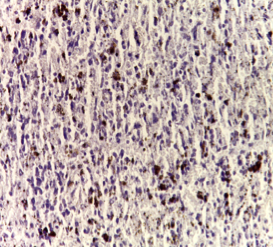

Histopathological studies

Histological examination of the spleen from the normal control group revealed normal histological architecture as shown in fig. 3a. Spleen tissue from rats from DMN group revealed deviation from normality. Deviations were detected on both macroscopical and microscopical levels. Macroscopical changes were observed in the form of enlargement in the size of an organ after four weeks. Histological examination was characterized by early degenerative changes in the white pulp (fig. 3b) and hemorrhage in blood sinusoids (fig. 3c). Dilated blood vessels with the stagnation of blood and thickened trabecular walls that were lined by inflammatory cells were also a prominent feature (fig. 3d). In addition, hyaline material within congested sinusoids was realized with an aggregation of deeply stained lymphocytes within the red pulp (fig 3e). Moreover, enlargement in the Malpighian bodies, harboring deeply stained lymphocytes encircled by a narrow band of paler stained epithelial cells were also noticed. Necrotic areas were evident along with the whole splenic tissue and haemorrhagic changes were also prominent where red blood cells invaded sinusoidal spaces (fig. 3f).

Spleen tissue of animals of the group injected with PRP manifested slight damage as designated by degeneration in the white pulps. Signs of recovery were inspected in some areas. This was represented in the reappearance of well-observed malpighian corpuscles (fig. 3g), which seemed similar to normal architecture. The spleen appeared to partially regain its splenic architecture (fig. 3g).

As QUR was orally administrated to DMN group, mild signs of recovery appeared as the degenerative changes in the white pulp and hemorrhage in blood sinusoids still appeared and red blood cells appeared in the sinousoidal spaces (fig. 3h).

Fig. 3(a- h): Histological examination of spleen (H & E.), (a) Normal control group showing normal spleen architecture (X100), (b-f) DMN group showing: (b) degenerative changes with loss of contour of white pulp (X100); (c) haemorrhage in blood sinusoids (X100); (d) Dilated blood vessels with stagnation of blood and thickened trabecular walls lined by inflammatory cells (X400); (e) hyaline material within congested sinusoids and aggregation of deeply stained lymphocytes within the red pulp (X400) and (f) Necrotic areas along whole splenic tissue and red blood cells invaded sinusoidal spaces (X400). (g) PRP injected to DMN group showing reappearance of well-observed malpighian corpusles (X100). (h) QUR administrated to DMN group showing haemorrhage and red blood cells in blood sinusoids (X400).